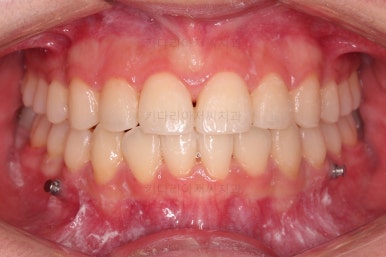

전후사진을 비교해볼게요.

약간의 주걱턱, 돌출입은 고칠 의사가 없어서 그대로 유지하였고 주걱턱 패턴으로 인한 부정교합 부분을 개선했으며 무엇보다 중요한 것은 쓰러져서 많이 썩어있던 치아를 자칫 치료 못할 뻔 했는데 교정치료와 병행하여 훌륭하게 치료하여 살려 썼다는 점이었어요.

그리고 사랑니 발치 + 충치치료 + 교정치료 모든 것이 키다리아저씨치과 한 곳에서 다 가능하다는 점이 저희 치과의 매우 큰 장점이지요.